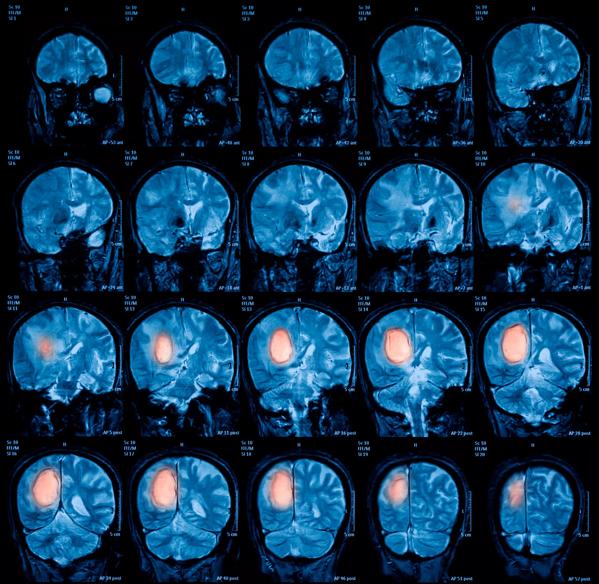

Magnetic resonance imaging (MRI) of the brain, brain tumor

A new study by Cleveland Clinic researchers has uncovered some of the mystery behind what enables glioblastoma – one of the most deadly and recurring brain cancers – to resist most cancer treatments, including chemotherapy, radiation and immunotherapy.